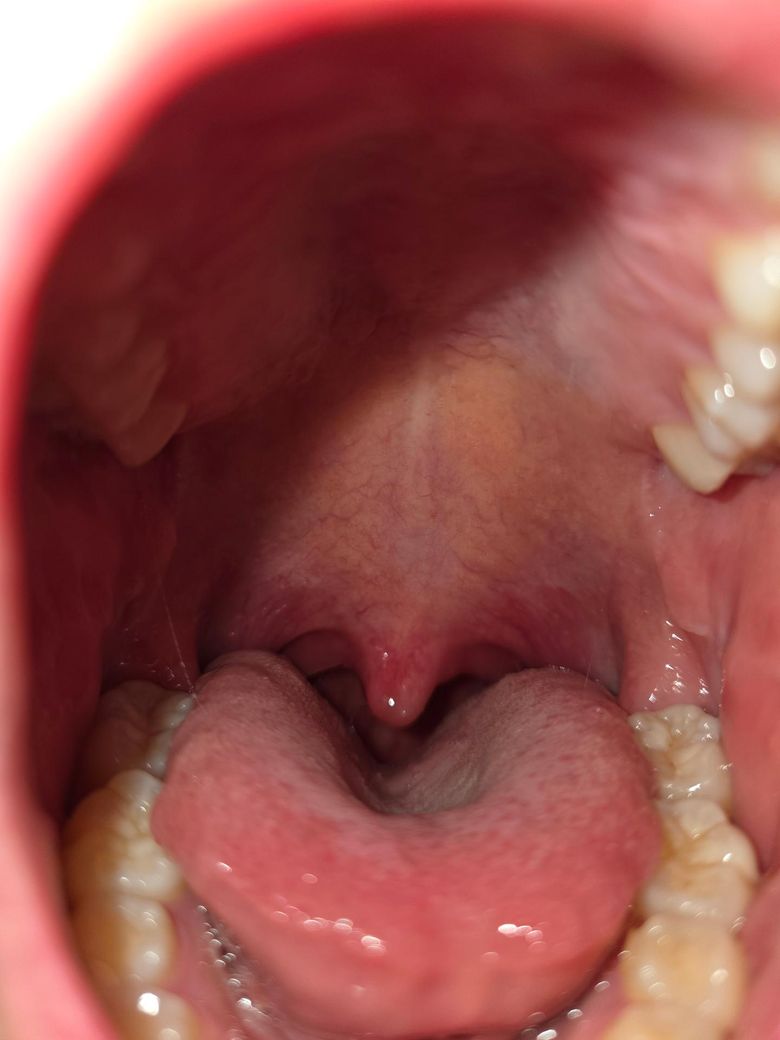

사진상으로 봤을 때 목이 부은 건가요?

침삼킬때 너무 아파서 잠도 제대로 못 잤습니다..

탁센을 먹으면 좀 괜찮아질까요?? 편도? 가 부은 건가요?

• 1번 째 사진

• 사진 기준으로 보면 편도 자체가 크게 부어 있거나 백태가 뚜렷한 편도염 소견은 아닙니다. 대신 연구개와 인두 뒤쪽 점막이 전반적으로 충혈돼 있고 부어 있어 급성 인두염 또는 인후두염 쪽이 더 타당해 보입니다. 이런 경우 침 삼킬 때 특히 심한 통증이 생기고, 밤에 누우면 통증이 더 도드라질 수 있습니다.

탁센(덱시부프로펜)은 통증 완화에는 도움이 될 수 있습니다. 다만 위장 자극이 있을 수 있으니 공복 복용은 피하는 게 좋습니다. 항생제가 필요한 전형적인 세균성 편도염 소견은 현재 사진상 뚜렷하지 않아 보이며, 이 경우에는 진통·소염과 국소 관리가 우선입니다.

당분간은 따뜻한 수분 섭취, 자극적인 음식·술·카페인 회피, 소금물 가글 또는 인후 스프레이 사용, 말 사용 최소화가 도움이 됩니다. 통증이 3–4일 이상 지속되거나 점점 심해지거나, 고열·침도 삼키기 어려울 정도의 통증·호흡 불편이 동반되면 이비인후과 진료가 필요합니다.

혀에 가려져서 편도가 보이지는 않지만, 편도가 커져 있다면 그래도 보입니다. 현재로서는 편도는 정상이라고 보입니다. 목젖에 가려서 인후 부위는 보이지는 않아요. 일단 문의 주신 소염 진통제 드시면서 따뜻한 물도 자주 마시고 지켜보시지요.